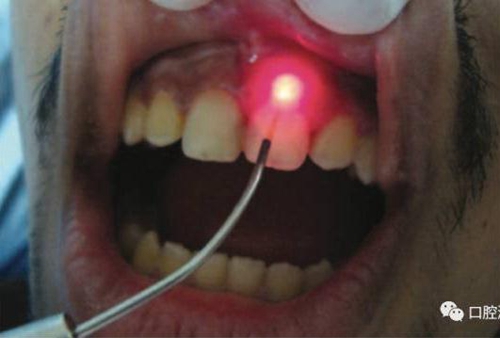

對(duì)瘺管位置進(jìn)行激光氣化

激光治療后即刻